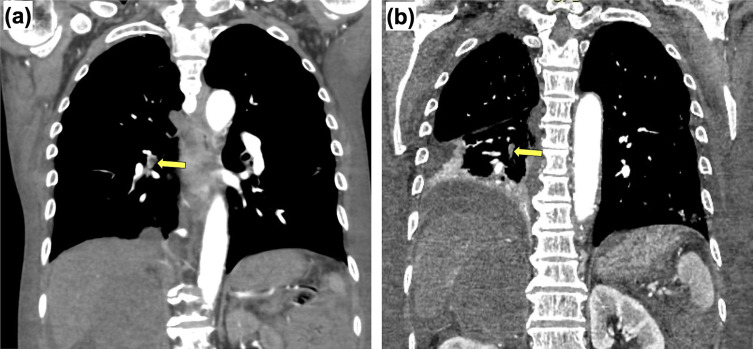

一名 78 岁的日本老人因咽喉痛和发烧到急诊科就诊,3 周后病情加重。扁桃体活检后确诊为多形性套细胞淋巴瘤(MCL),已浸润右肾上腺、下腔静脉和右心房(RA)。虽然患者的心脏肿瘤具有很高的移动性,但他的血流动力学状态稳定,没有出现致命性心律失常。因此,我们首先进行了化疗。然而,患者出现了复发性肺栓塞(PE),并在开始化疗后死亡。尸检显示,MCL 侵犯了大血管,导致了肺栓塞。尽管众所周知心脏肿瘤的高流动性会增加弥漫大B细胞淋巴瘤(DLBCL)发生肺栓塞的风险,但由于其罕见性,心脏MCL的最佳治疗方法仍有待阐明。据我们所知,这是日本患者首次报告治疗后出现 PE 的心脏 MCL。不仅是 DLBCL,基于心脏肿瘤的流动性,MCL 也值得考虑在治疗前进行预防性手术。我们的病例强调了血液科医生和心脏科医生在治疗心脏型 MCL 时密切沟通的必要性。

A 78-year-old Japanese man presented to the emergency department with a sore throat and fever that worsened over 3 weeks. A tonsil biopsy led to the diagnosis of pleomorphic mantle cell lymphoma (MCL) that had infiltrated the right adrenal gland, inferior vena cava, and right atrium (RA). Although the patient's cardiac tumor had high mobility, his hemodynamic state was stable, and he did not present with fatal arrhythmia. Therefore, we first introduced chemotherapy. However, the patient developed recurrent pulmonary embolisms (PEs) and died after starting chemotherapy. An autopsy revealed that the MCL had invaded the large vessels, causing the PEs. Although the high mobility of cardiac tumors is known to increase the risk of PE in diffuse large B-cell lymphoma (DLBCL), optimal management of cardiac MCL remains to be elucidated owing to its rarity. To the best of our knowledge, this is the first report of cardiac MCL with posttreatment PE development in a Japanese patient. It is worth considering preventive surgery before treatment not only in DLBCL, but also in MCL based on the mobility of the cardiac tumors. Our case highlights the need for close communication between hematologists and cardiologists to treat cardiac MCL.